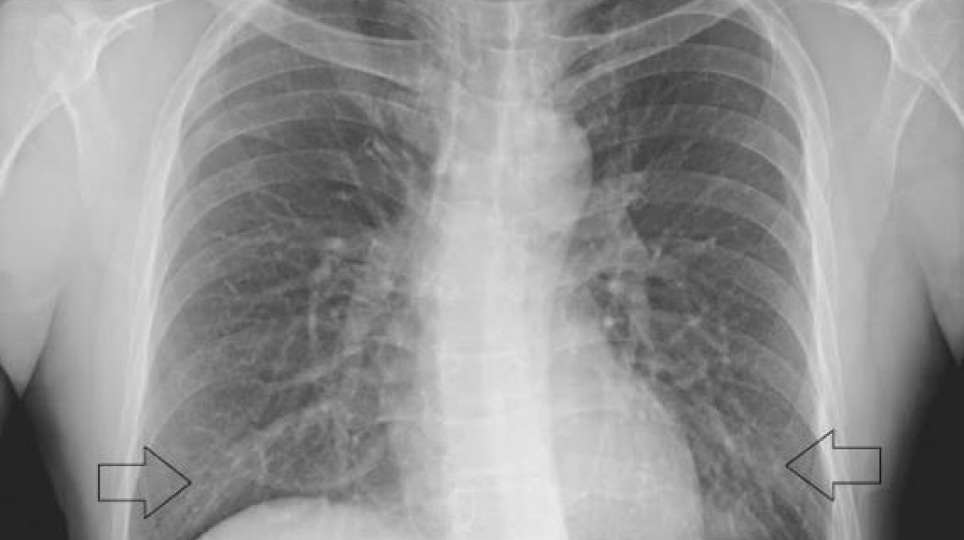

吸菸與新冠肺炎有劑量效應,進一步確認其相關性